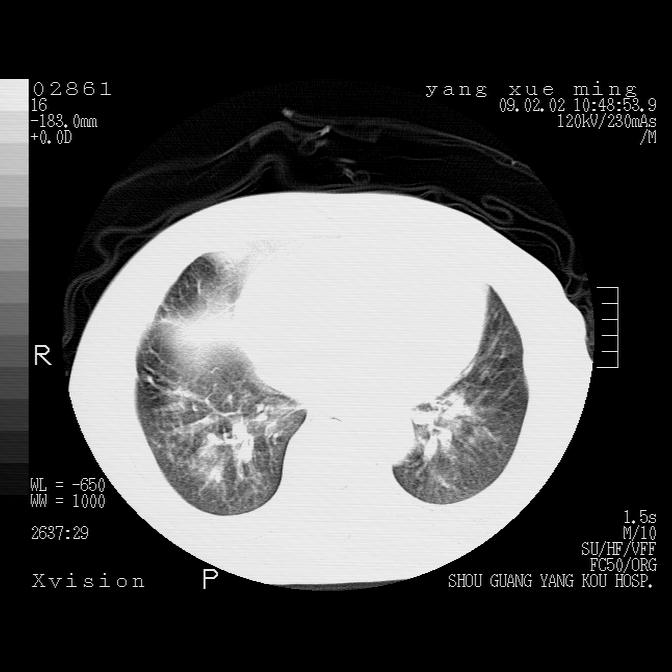

以下是引用lkc8963在2009-2-3 20:11:00的发言:[br]1)右上肺陈旧病灶。2)右下肺团块及团片影,影像表现符合感染。3)左心增大,左冠脉钙化,符合冠心病。4)双侧肺门扩大,以左侧为著,肺动脉干略粗,左上肺局限性气肿,为谨慎起见,需除肿瘤,建议增强。

以下是引用zbp537在2009-2-3 19:08:00的发言:[br]我诊断为肺泡性肺水肿。[br]诊断依据:[br]1、心影普遍增大,肺血管增粗,并见絮状高密度影,肺门改变显著。[br]2、临床上表现胸闷咳嗽,无发烧,不是一个典型的肺部感染的病史。

以下是引用王仕学在2009-2-3 20:28:00的发言:[br]考虑右下肺感染,建议治疗后复查。